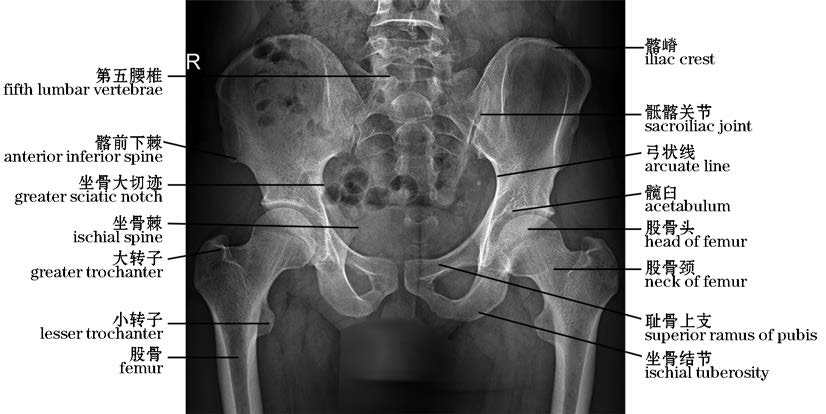

图2-36 男性骨盆X线片(正位)

The anteroposterior view radiograph of pelvis,X-rays(male)